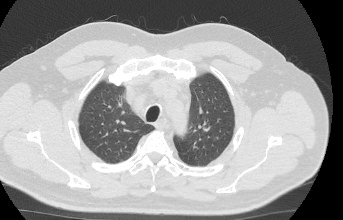

Мультиспиральная компьютерная томография органов грудной клетки представляет собой рентгеновское исследование костных структур грудной клетки, легочной ткани, бронхиального дерева, органов средостения.

Информативность МСКТ органов грудной клетки дополняет функциональная проба, то есть методика проведения сканирования на вдохе (инспираторная КТ) и на выдохе (экспираторная КТ). При выполнении КТ на вдохе с задержкой дыхания удается добиться максимального контраста между наполненными воздухом легкими и более плотными структурами, такими как плевра, стенки бронхов и кровеносные сосуды. Кроме того, на фоне пневматизированных легких хорошо видны очаговые и диффузные патологические изменения.

При экспираторной пробе (пробе на выдохе) можно выявить воздушные ловушки (то есть стойкое повышение пневматизации легочной ткани) на фоне пневмонитов, бронхиолитов, обструктивных заболеваний легких, эмфиземы.

Компьютерная томография в нашей клинике проводится на современных мультиспиральных томографах, которые производят тончайшие срезы исследуемой области и создают трехмерные изображения всех структур грудной клетки высокой четкости и контрастности. Увеличенное количество детекторов, которыми оснащены аппараты, обеспечивают быстрое сканирование зоны исследования при минимальных дозах рентгеновского облучения.